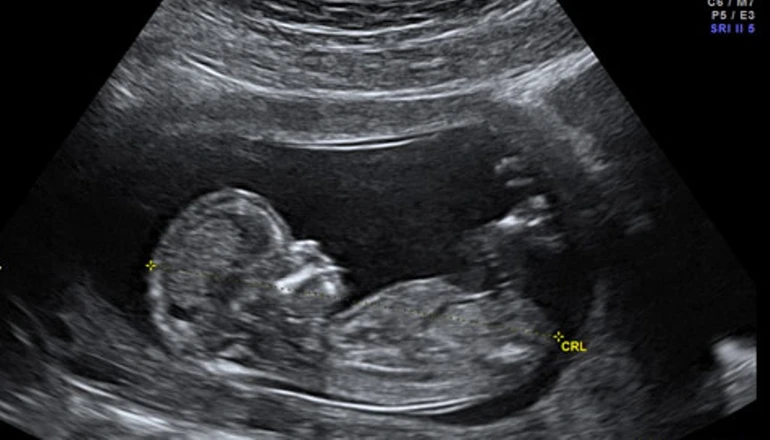

Thời điểm được cho là bắt đầu sự sống, chính xác là hình thành bào thai (con người) hiện trên thế giới có nhiều quan điểm khác nhau. Theo Phật giáo, có ba nhân tố căn bản hòa hợp để hình thành nên bào thai. Đó là do tinh cha, huyết mẹ cùng thần thức hòa hợp mà thành.

Như vậy có thể xác định, thời khắc tinh trùng xâm nhập vào trứng (cả tự nhiên cùng các phương pháp thụ tinh nhân tạo, thụ tinh trong ống nghiệm) đồng thời thần thức (hương ấm) phải có mặt để cùng hội nhập, chính là lúc đầy đủ nhân duyên để hình thành bào thai.